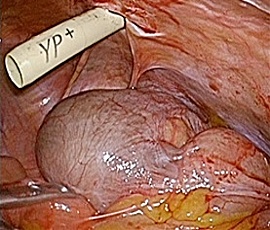

[静脈硬化性大腸炎(特発性腸間膜静脈硬化症)] 手術:腹腔鏡下結腸切除術

約6年前より繰り返す右側腹部痛と下痢を主訴にて精査目的に受診。腹部レントゲン検査にて、右側結腸の腸間膜側に一致した石灰化を認め、精査の結果、典型的な結腸辺縁静脈の石灰化と診断。手術(腹腔鏡下結腸切除術)を施行した。病理診断結果は、静脈硬化性大腸炎であった。

手術画像